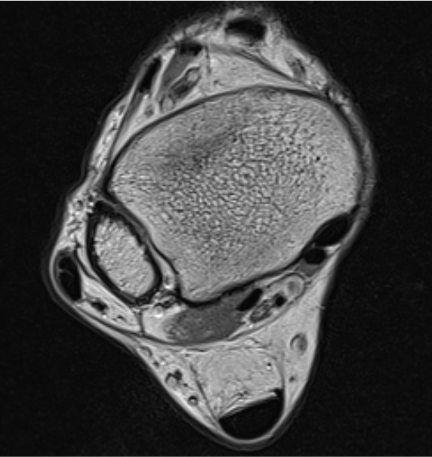

MRI

Anterior subluxation of peroneal tendons

Anterior subluxation of peroneal tendons

Predisposition

- MRI and CT of 30 patients with peroneal dislocation

- compared to 30 controls

- no difference in retromalleolar groove

- peroneal dislocation associated with low lying PB muscle belly